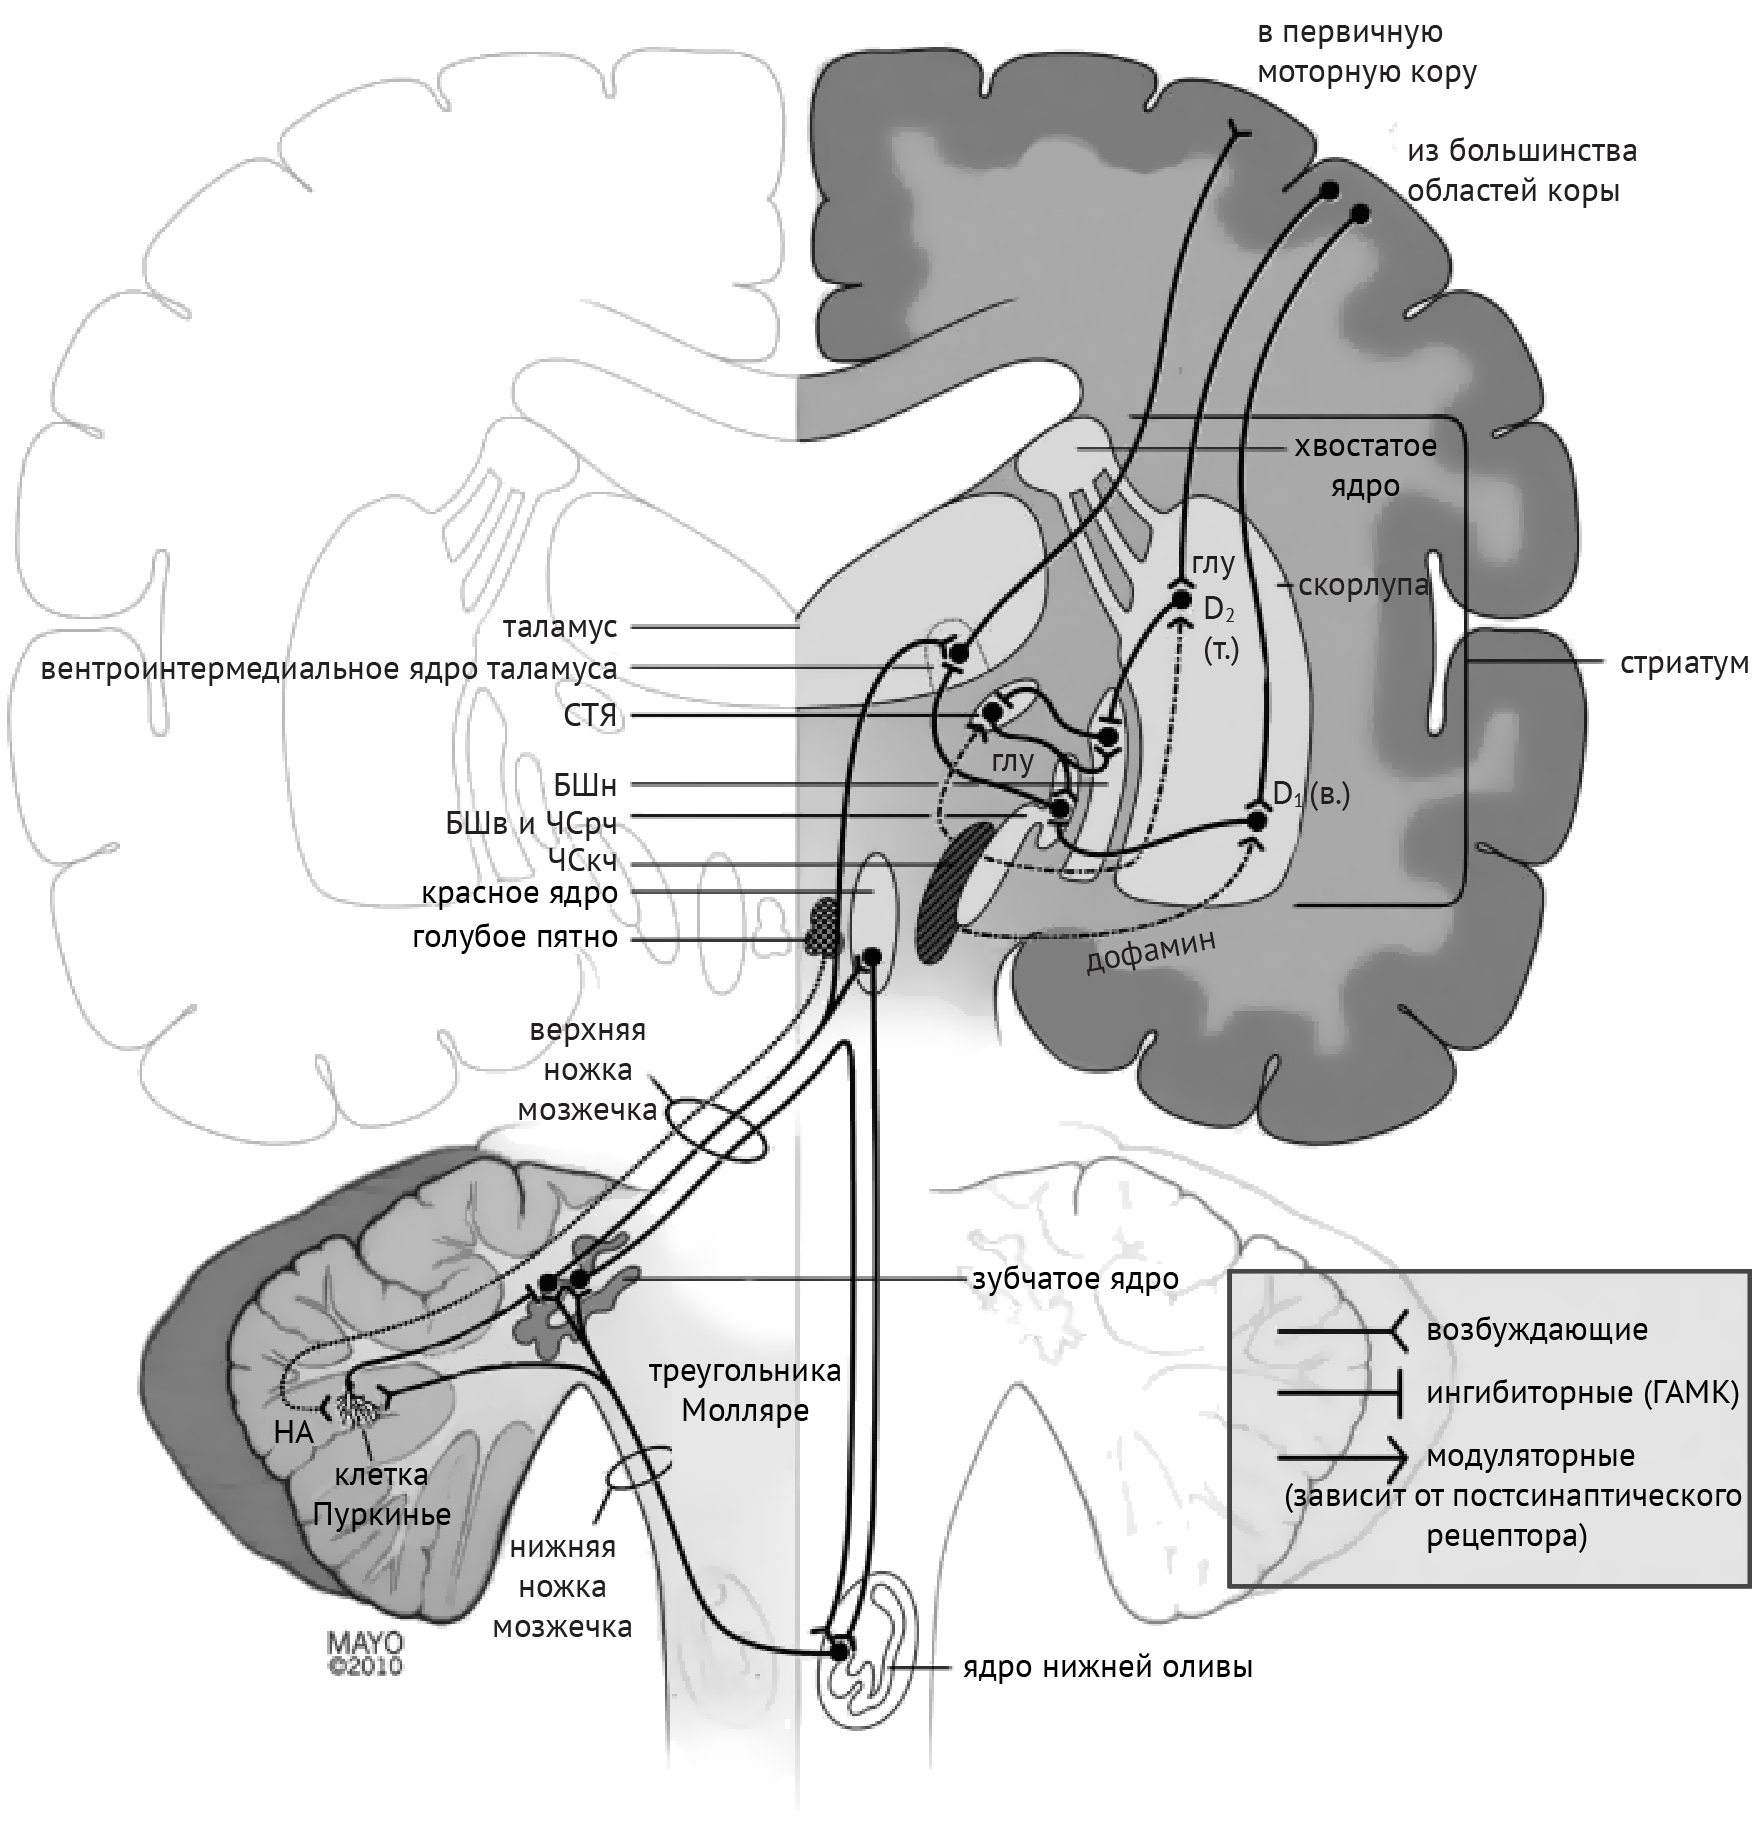

В рамках реализации программы экстрапирамидной системы наибольшее внимание отдается циклу «кора — базальные ганглии — таламус» (рис.1). Полосатое тело отправляет ГАМК-ергические сигналы к бледному шару (БШ), обусловливая растормаживание таламуса через прямой путь и снижая его активность непрямым путем — через внутренний сегмент бледного шара (БШв) и субталамическое ядро (СТЯ). Компактная часть черной субстанции (ЧСкч) обеспечивает стимуляцию дофаминовых рецепторов полосатого тела, активируя прямой путь через дофаминовые рецепторы D1 (D1R) и подавляя непрямой путь через дофаминовые рецепторы D2 (D2R) (схема 1).

Дегенерация ЧСкч приводит к недостаточной активации полосатого тела через прямой путь и, как следствие, дезингибированию БШв, который, в свою очередь, подает ингибирующие сигналы в таламус. Недостаточное ингибирование через непрямой путь ведет к подавлению БШн и дезингибированию СТЯ, которое активирует БШв (схема 2).

Среди патологий, обсуждаемых в медицинских вузах, патогенез хореиформных гиперкинезов рассматривался следующим образом: локальная, но выраженная дегенерация шипиковых нейронов стриатума, проецирующихся на БШн, приводит к его дезингибированию, в результате чего угнетается активирующая деятельность СТЯ в отношении БШв и ингибиторная деятельность БШв в отношение таламуса (схема 3).

Если говорить о баллизме, то причиной развития этого синдрома будет являться поражение СТЯ. В таком случае, отсутствие стимуляции БШв со стороны СТЯ обусловливает недостаточную ингибирующую активность в отношении таламуса, что, в свою очередь, и реализуется в виде гиперкинеза.

Дистония — явление недостаточной ингибирующей активности, обусловленное поражением БШв и приводящее к дезингибированию таламуса и избыточной активации коры (схема 4).